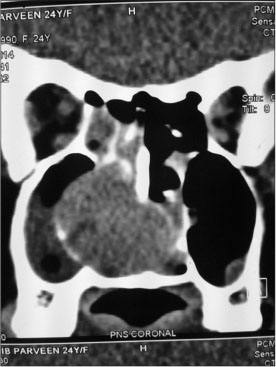

|?Figure. 5? Computed tomography scan showing a mass lesion in the right side of nasal cavity; further biopsy and immunohistochemistry confirmed it as Ewing?s sarcoma